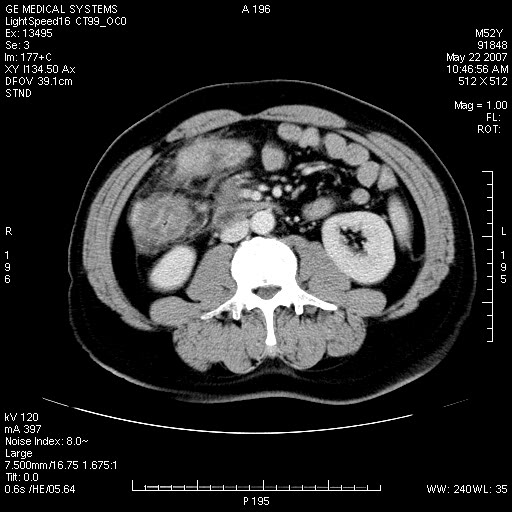

以下是引用余辉在2007-5-22 20:12:00的发言:[br]升结肠管壁明显增厚,增强有静脉期持续增强,结合患者病史,考虑结肠癌可能性大,临近脂肪影密度增高,混浊,恐有肠系膜浸润转移,建议镜检

以下是引用dyqct在2007-5-22 20:43:00的发言:[br]支持结肠肝曲占位性病变(浸润型结肠癌可能性大)。胆总管下端扩张,原因待查。

以下是引用gaoxiao在2007-5-22 20:49:00的发言:[br]考虑升结肠癌向周围侵犯,胰头钩突受侵。